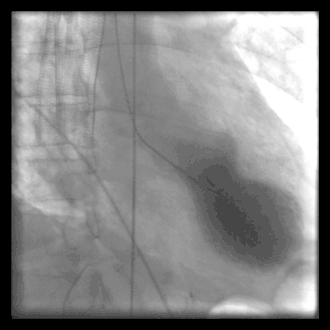

A common example of cardiac catheterization is coronary catheterization that involves catheterization of the coronary arteries for coronary artery disease and myocardial infarctions ("heart attacks"). Catheterization is most often performed in special laboratories with fluoroscopy and highly maneuverable tables. These "cath labs" are often equipped with cabinets of catheters, stents, balloons, etc. of various sizes to increase efficiency. Monitors show the fluoroscopy imaging, electrocardiogram (ECG), pressure waves, and more.

Coronary angiography is a diagnostic procedure that allows visualization of the coronary vessels. Fluoroscopy is used to visualize the lumens of the arteries as a 2-D projection. Should these arteries show narrowing or blockage, then techniques exist to open these arteries. Percutaneous coronary intervention is a blanket term that involves the use of mechanical stents, balloons, etc. to increase blood flow to previously blocked (or occluded) vessels.

Cardiac catheterization often requires the use of fluoroscopy to visualize the path of the catheter as it enters the heart or as it enters the coronary arteries. The coronary arteries are known as "epicardial vessels" as they are located in the epicardium, the outermost layer of the heart.[2] The use of fluoroscopy requires radiopaque contrast, which in rare cases can lead to contrast-induced kidney injury (see Contrast-induced nephropathy). People are constantly exposed to low doses of ionizing radiation during procedures.[3] Ideal table positioning between the x-ray source and receiver, and radiation monitoring via thermoluminescent dosimetry, are two main ways of reducing a person's exposure to radiation.[3] People with certain comorbidities (people who have more than one condition at the same time) have a higher risk of adverse events during the cardiac catheterization procedure.[3] These comorbidity conditions include aortic aneurysm, aortic stenosis, extensive three-vessel coronary artery disease, diabetes, uncontrolled hypertension, obesity, chronic kidney disease, and unstable angina.[4]